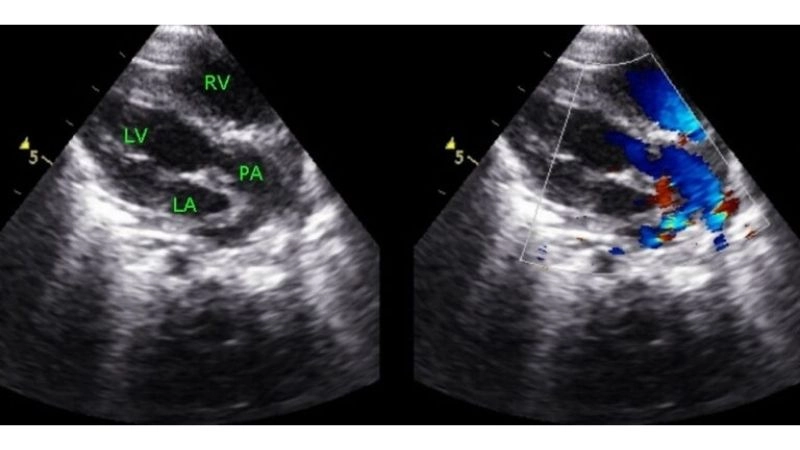

Images visual examples of transposition of the great arteries (TGA)

Transposition of the great arteries (TGA) is a congenital defect where the pulmonary artery and aorta switch positions, blocking normal oxygenation. Visual images highlight how this heart malformation develops.

Transposition of the great arteries echo key tool for diagnosis